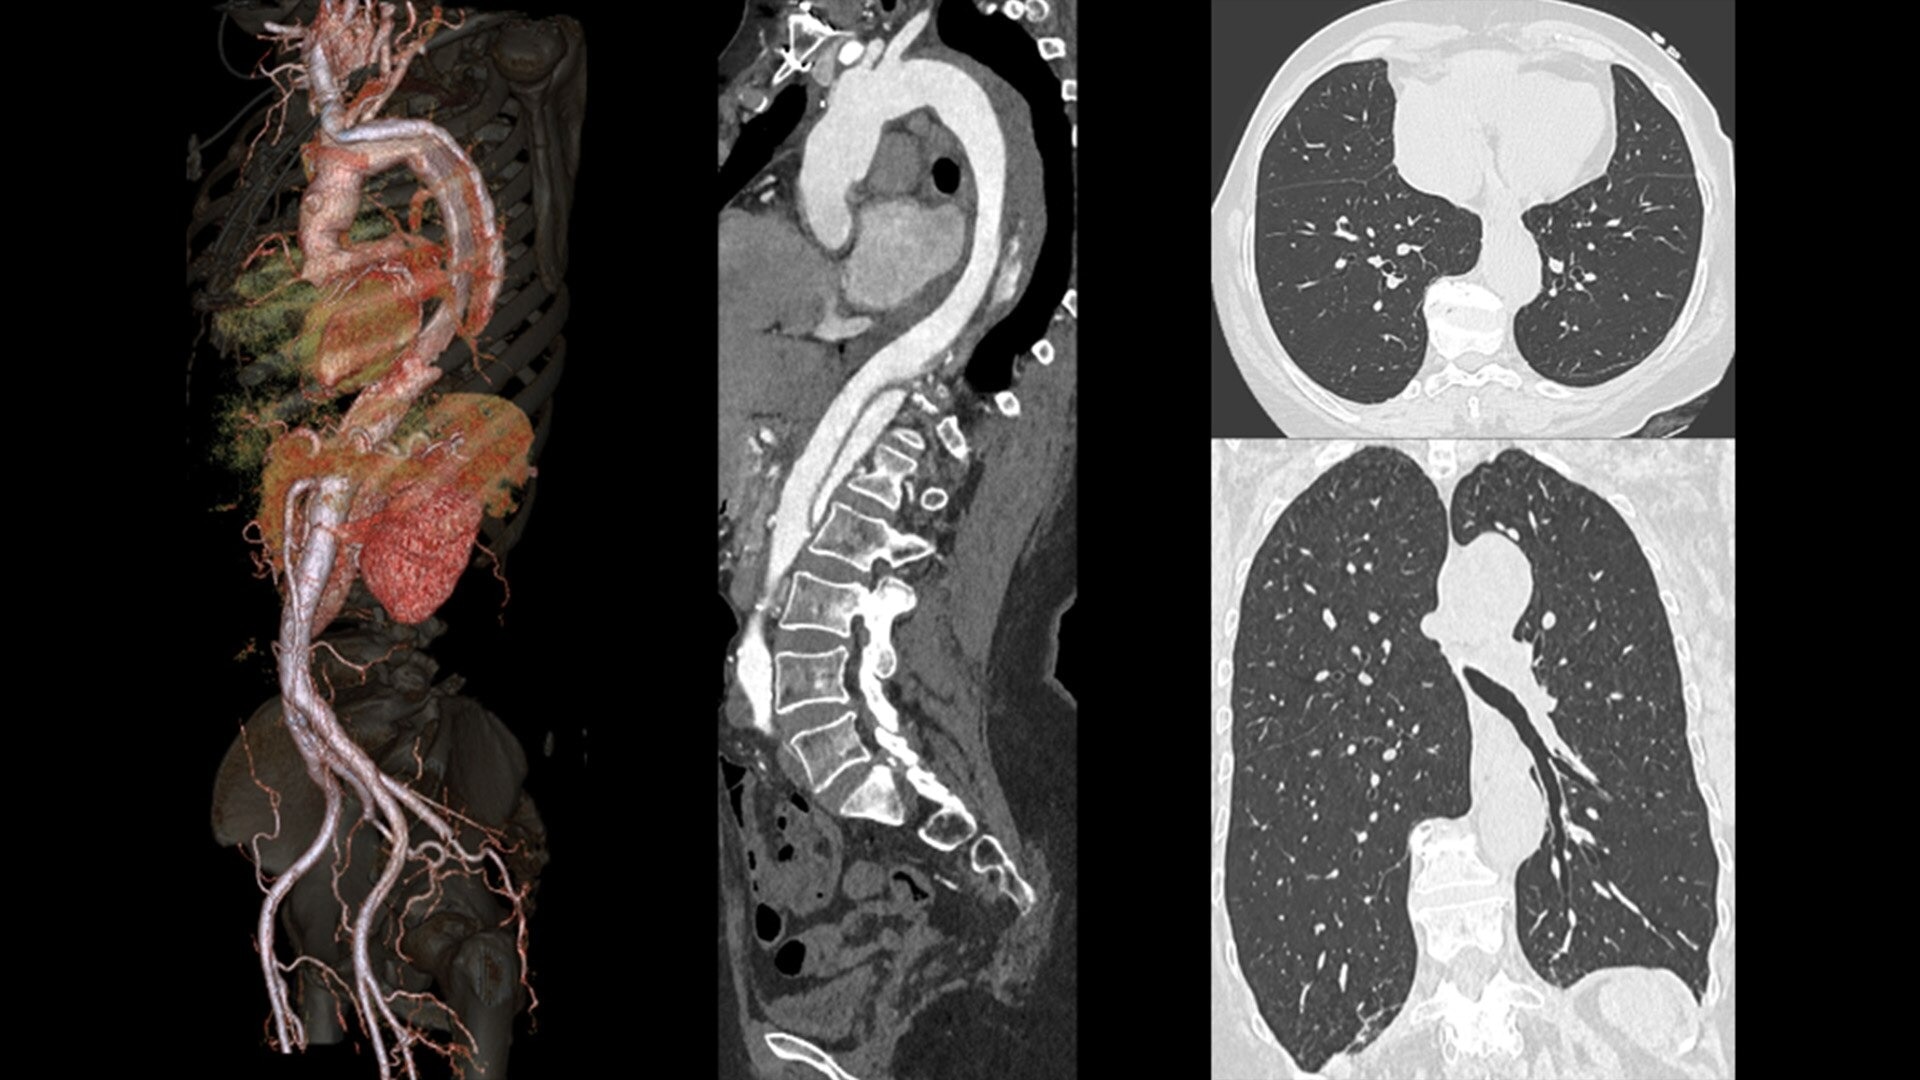

The ECG-less CT (a cardiac CT scan without an ECG trace) is an industry-first

Increases Cardiac CT access

Address cardiac exams where patient access and speed need to be prioritized

Simplified workflow

Useful in exams where excluding ECG traces would streamline patient preparation